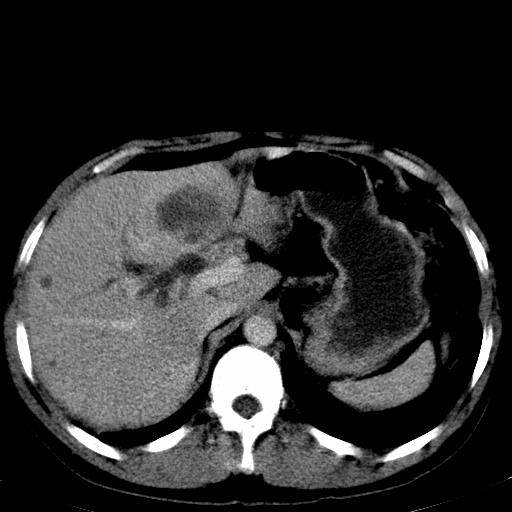

患者上腹部疼痛一月余,伴巩膜黄染;

考虑肝左叶胆管细胞癌侵犯肝门区并肝内胆管及肝总管扩张。

肝左叶肿块清度增强,所在的叶胆管扩张。考虑胆管细胞癌。

肝左叶胆管细胞癌侵犯肝门区并肝内胆管及肝总管扩张

考虑肝左叶胆管细胞癌侵犯肝门区并肝内胆管及肝总管扩张、肝门淋巴结肿大。